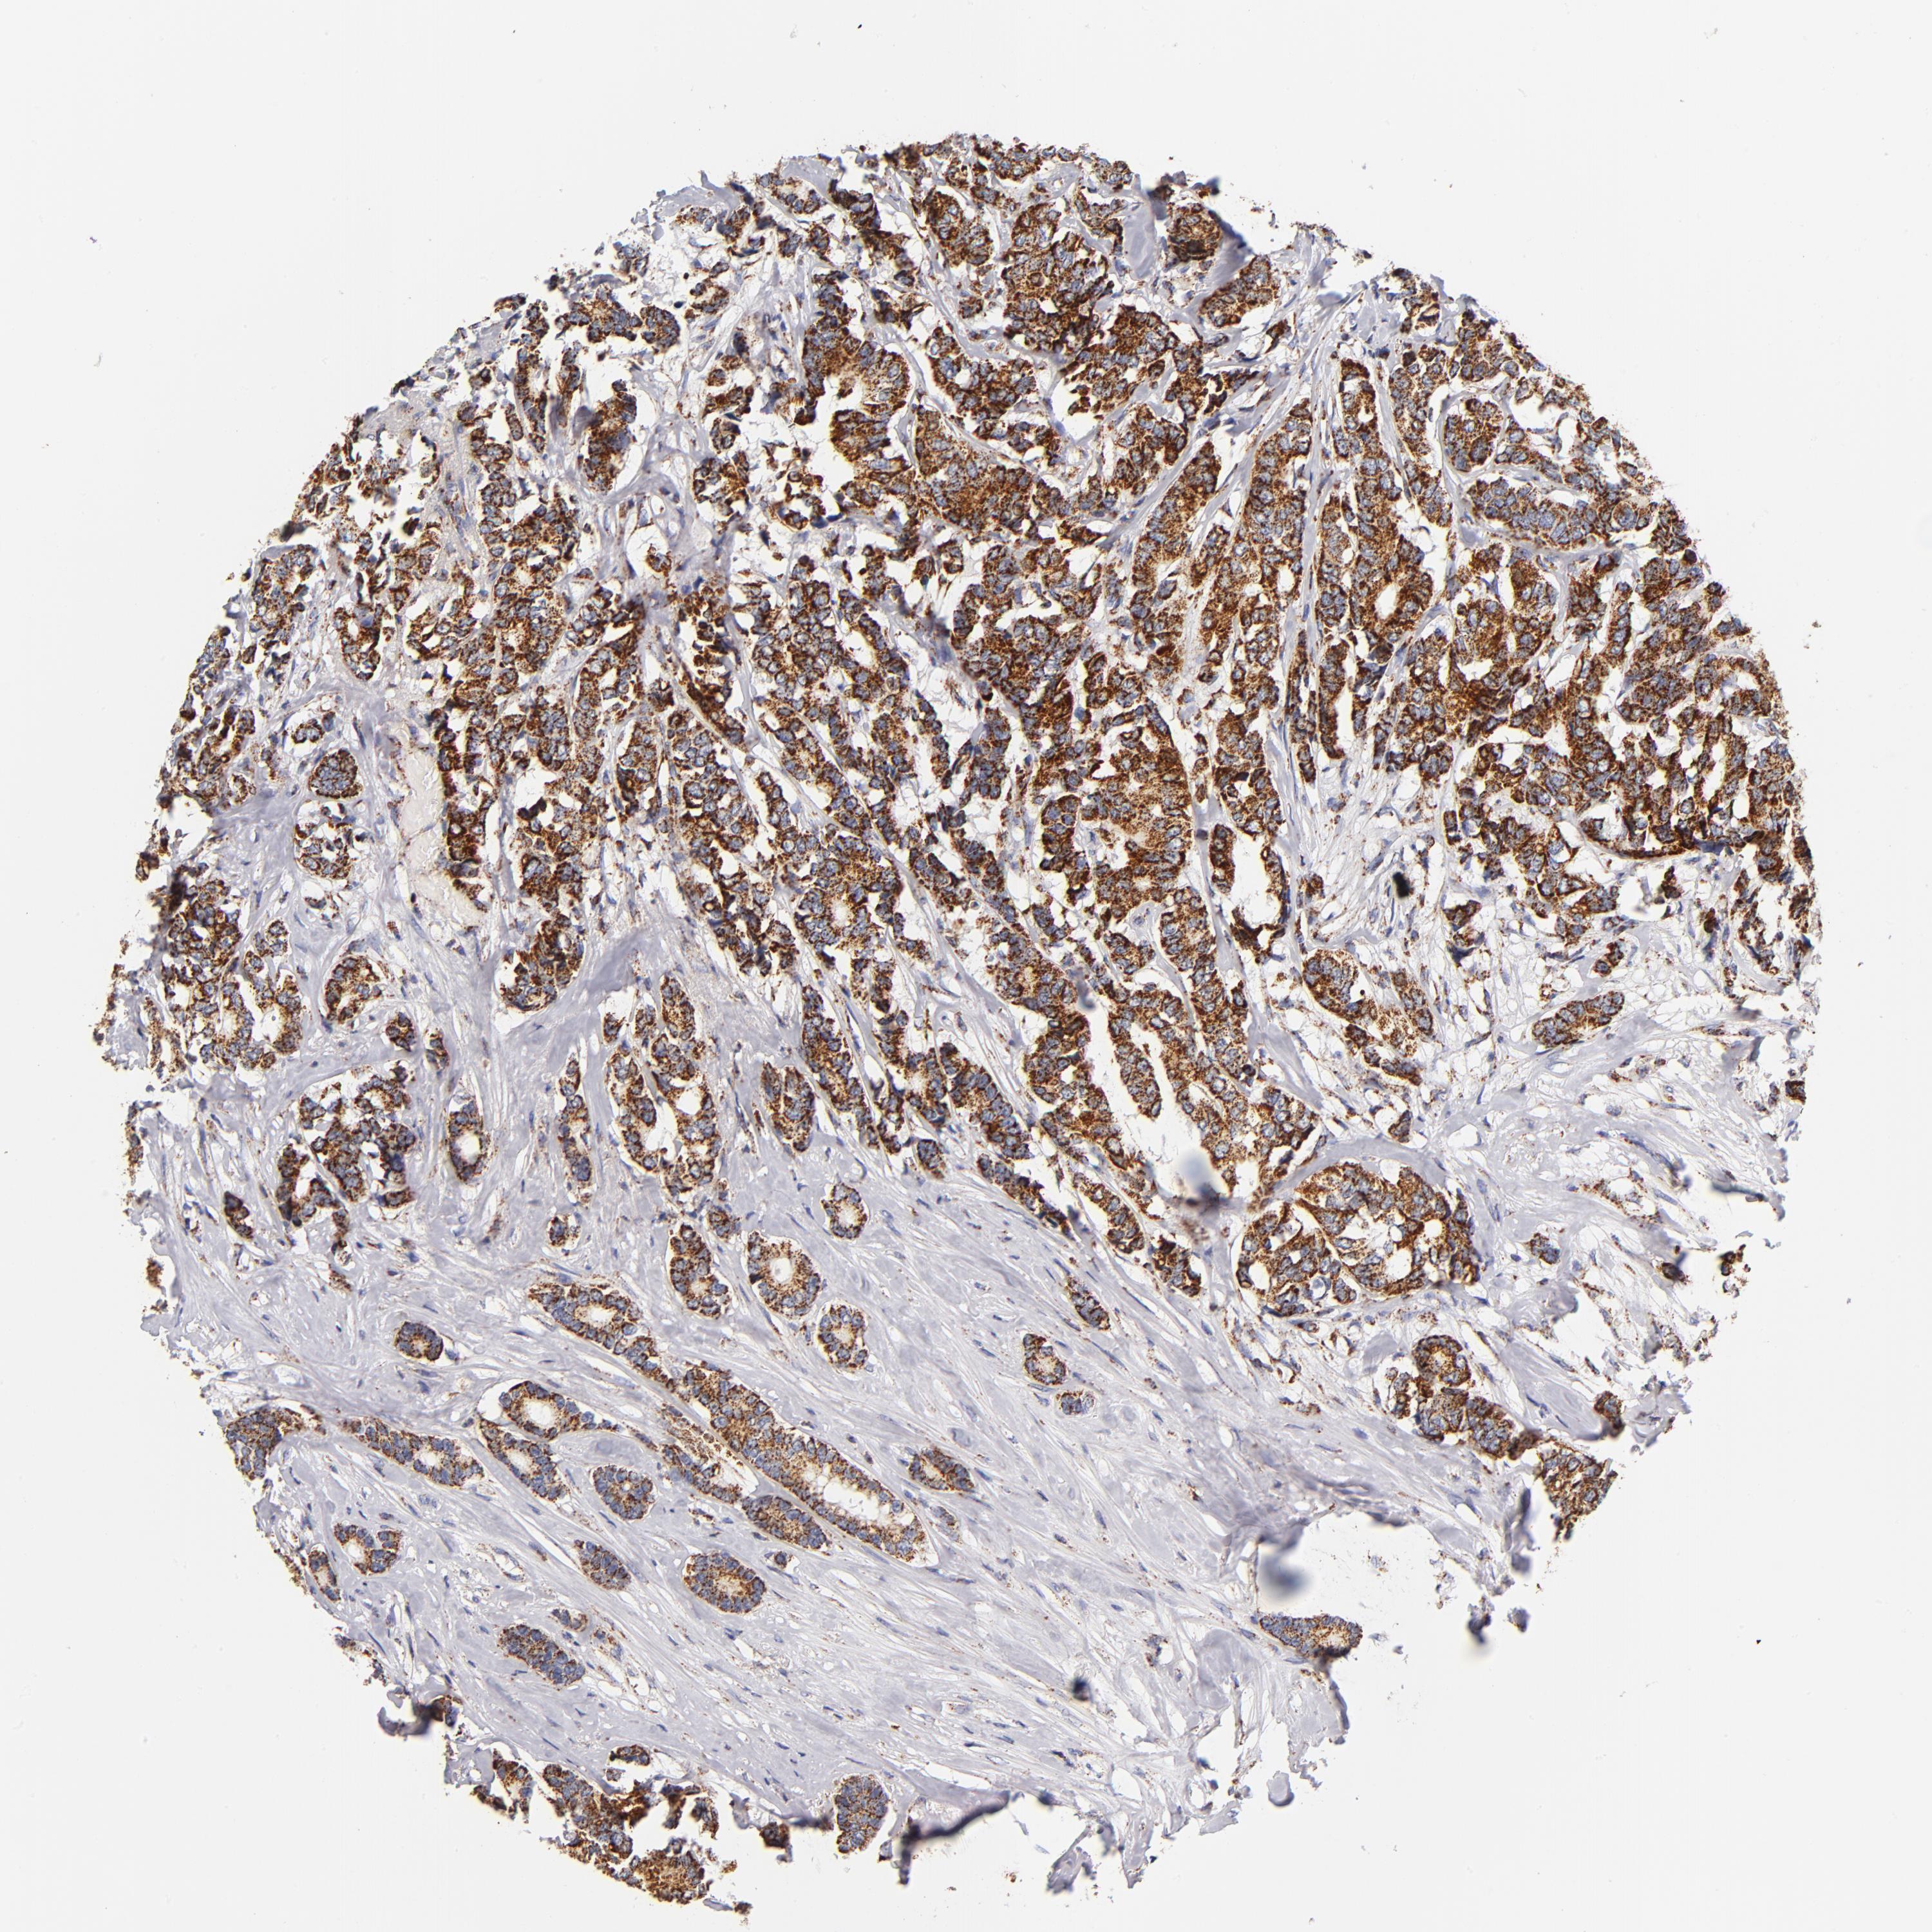

CANCER BREAST CANCER Show tissue menu

BRCA TCGA BRCA VALIDATION PROTEIN EXPRESSION

Breast cancer

Human cancer